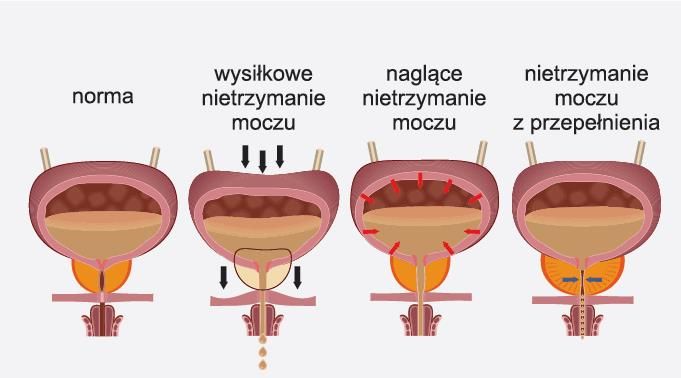

Ćwiczenie tych mięśni, to także jedna składowa z leczenia niewysiłkowego nietrzymania moczu zalecana również dla panów, nie tylko dla pań.

Każdego roku przybywa osób cierpiących z powodu nietrzymania moczu.

Myślę, że to kolejny krok który możemy zrobić dla siebie. Zapobiec bądź uleczyć okropne skrępowanie w miejscach publicznych, niewychodzenie do ludzi, (co jest w wielu przypadkach)